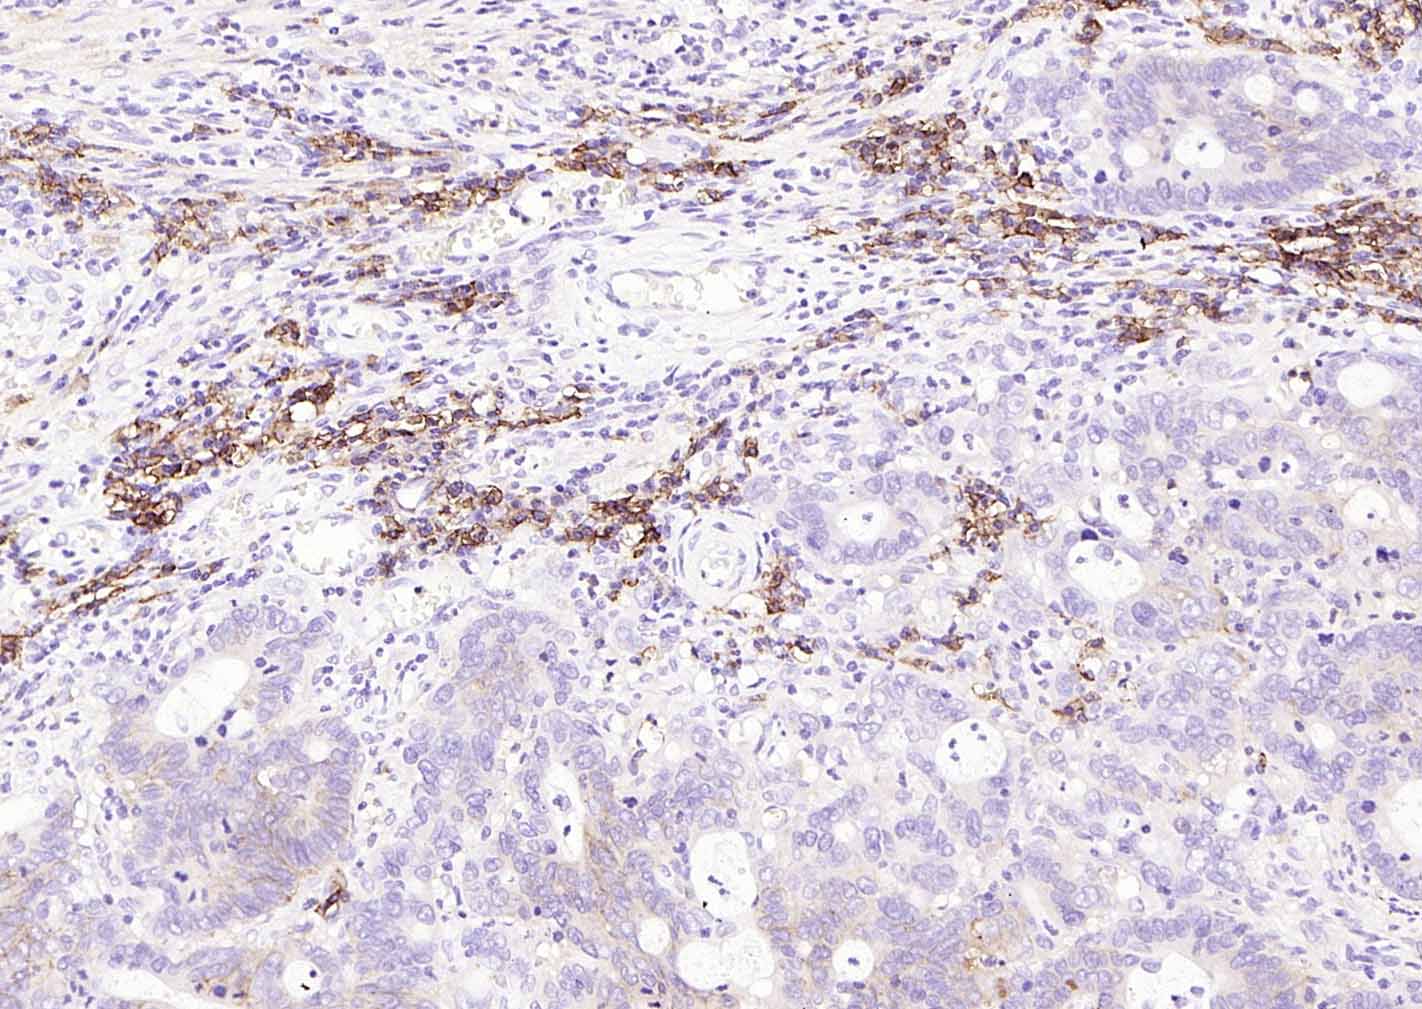

Paraformaldehyde-fixed, paraffin embedded (human colon carcinoma); Antigen retrieval by boiling in sodium citrate buffer (pH6.0) for 15min; Block endogenous peroxidase by 3% hydrogen peroxide for 20 minutes; Blocking buffer (normal goat serum) at 37°C for 30min; Incubation with (CD138) Monoclonal Antibody, Unconjugated (bsm-60902R) at 1:200 overnight at 4°C, followed by operating according to SP Kit(Rabbit) (sp-0023)instructionsand DAB staining.